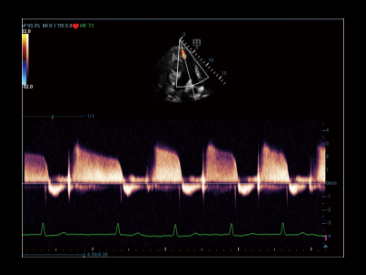

V-Flow

Векторный анализ кровотока в сосудах — это подход к оценке сосудистой гемодинамики, используя цветовой векторный анализ скорости движения и направления в каждой точке кровотока.